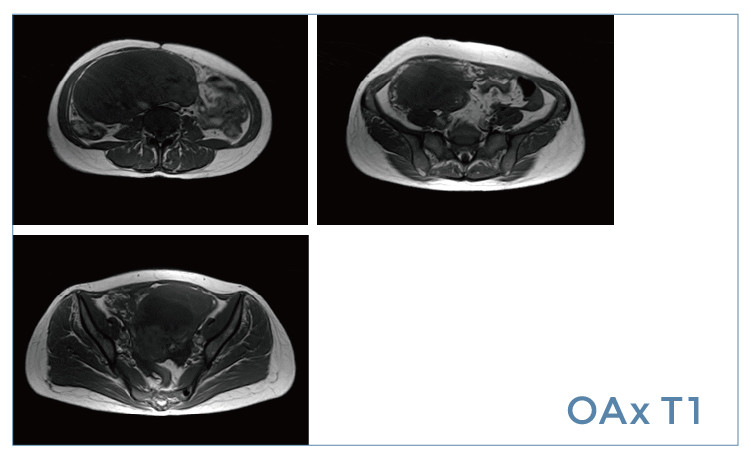

【朗润影像档案】20190426磁共振影像病例结果讨论

【朗润影像档案】磁共振影像病例分享(编号20190426)